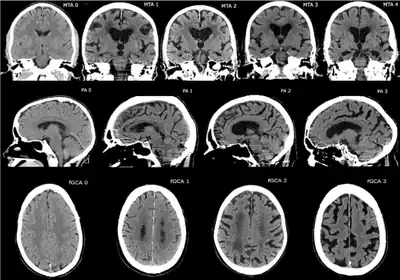

CT and MRI are most commonly used to observe the brain for cerebral atrophy. A CT scan takes cross sectional images of the brain using X-rays, while an MRI uses a magnetic field. With both measures, multiple images can be compared to see if there is a loss in brain volume over time.[19]